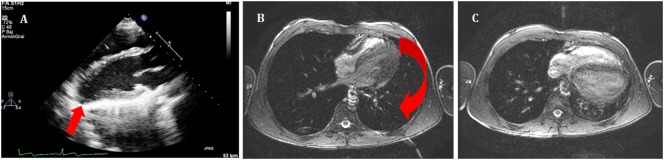

Figure 5 - Right parasternal echocardiogram showing anechoic pericardial effusion surrounding the heart with visible right atrial collapse during diastole. (A) Echocardiography in parasternal long axis. Arrow shows the posterior displacement of the apex and the lack of the typical round left ventricular apex. Cardiovascular magnetic resonance showing the clockwise rotation. Compared with the prone position (B), leftward posterior rotation of the heart is seen in when patient is in supine position (C).

Reference:Pérez-Casares A, Cesar S, Brunet-Garcia L, Sanchez-de-Toledo J. Echocardiographic Evaluation of Pericardial Effusion and Cardiac Tamponade. Front Pediatr. 2017 Apr 24;5:79. doi: 10.3389/fped.2017.00079. PMID: 28484689; PMCID: PMC5401877.